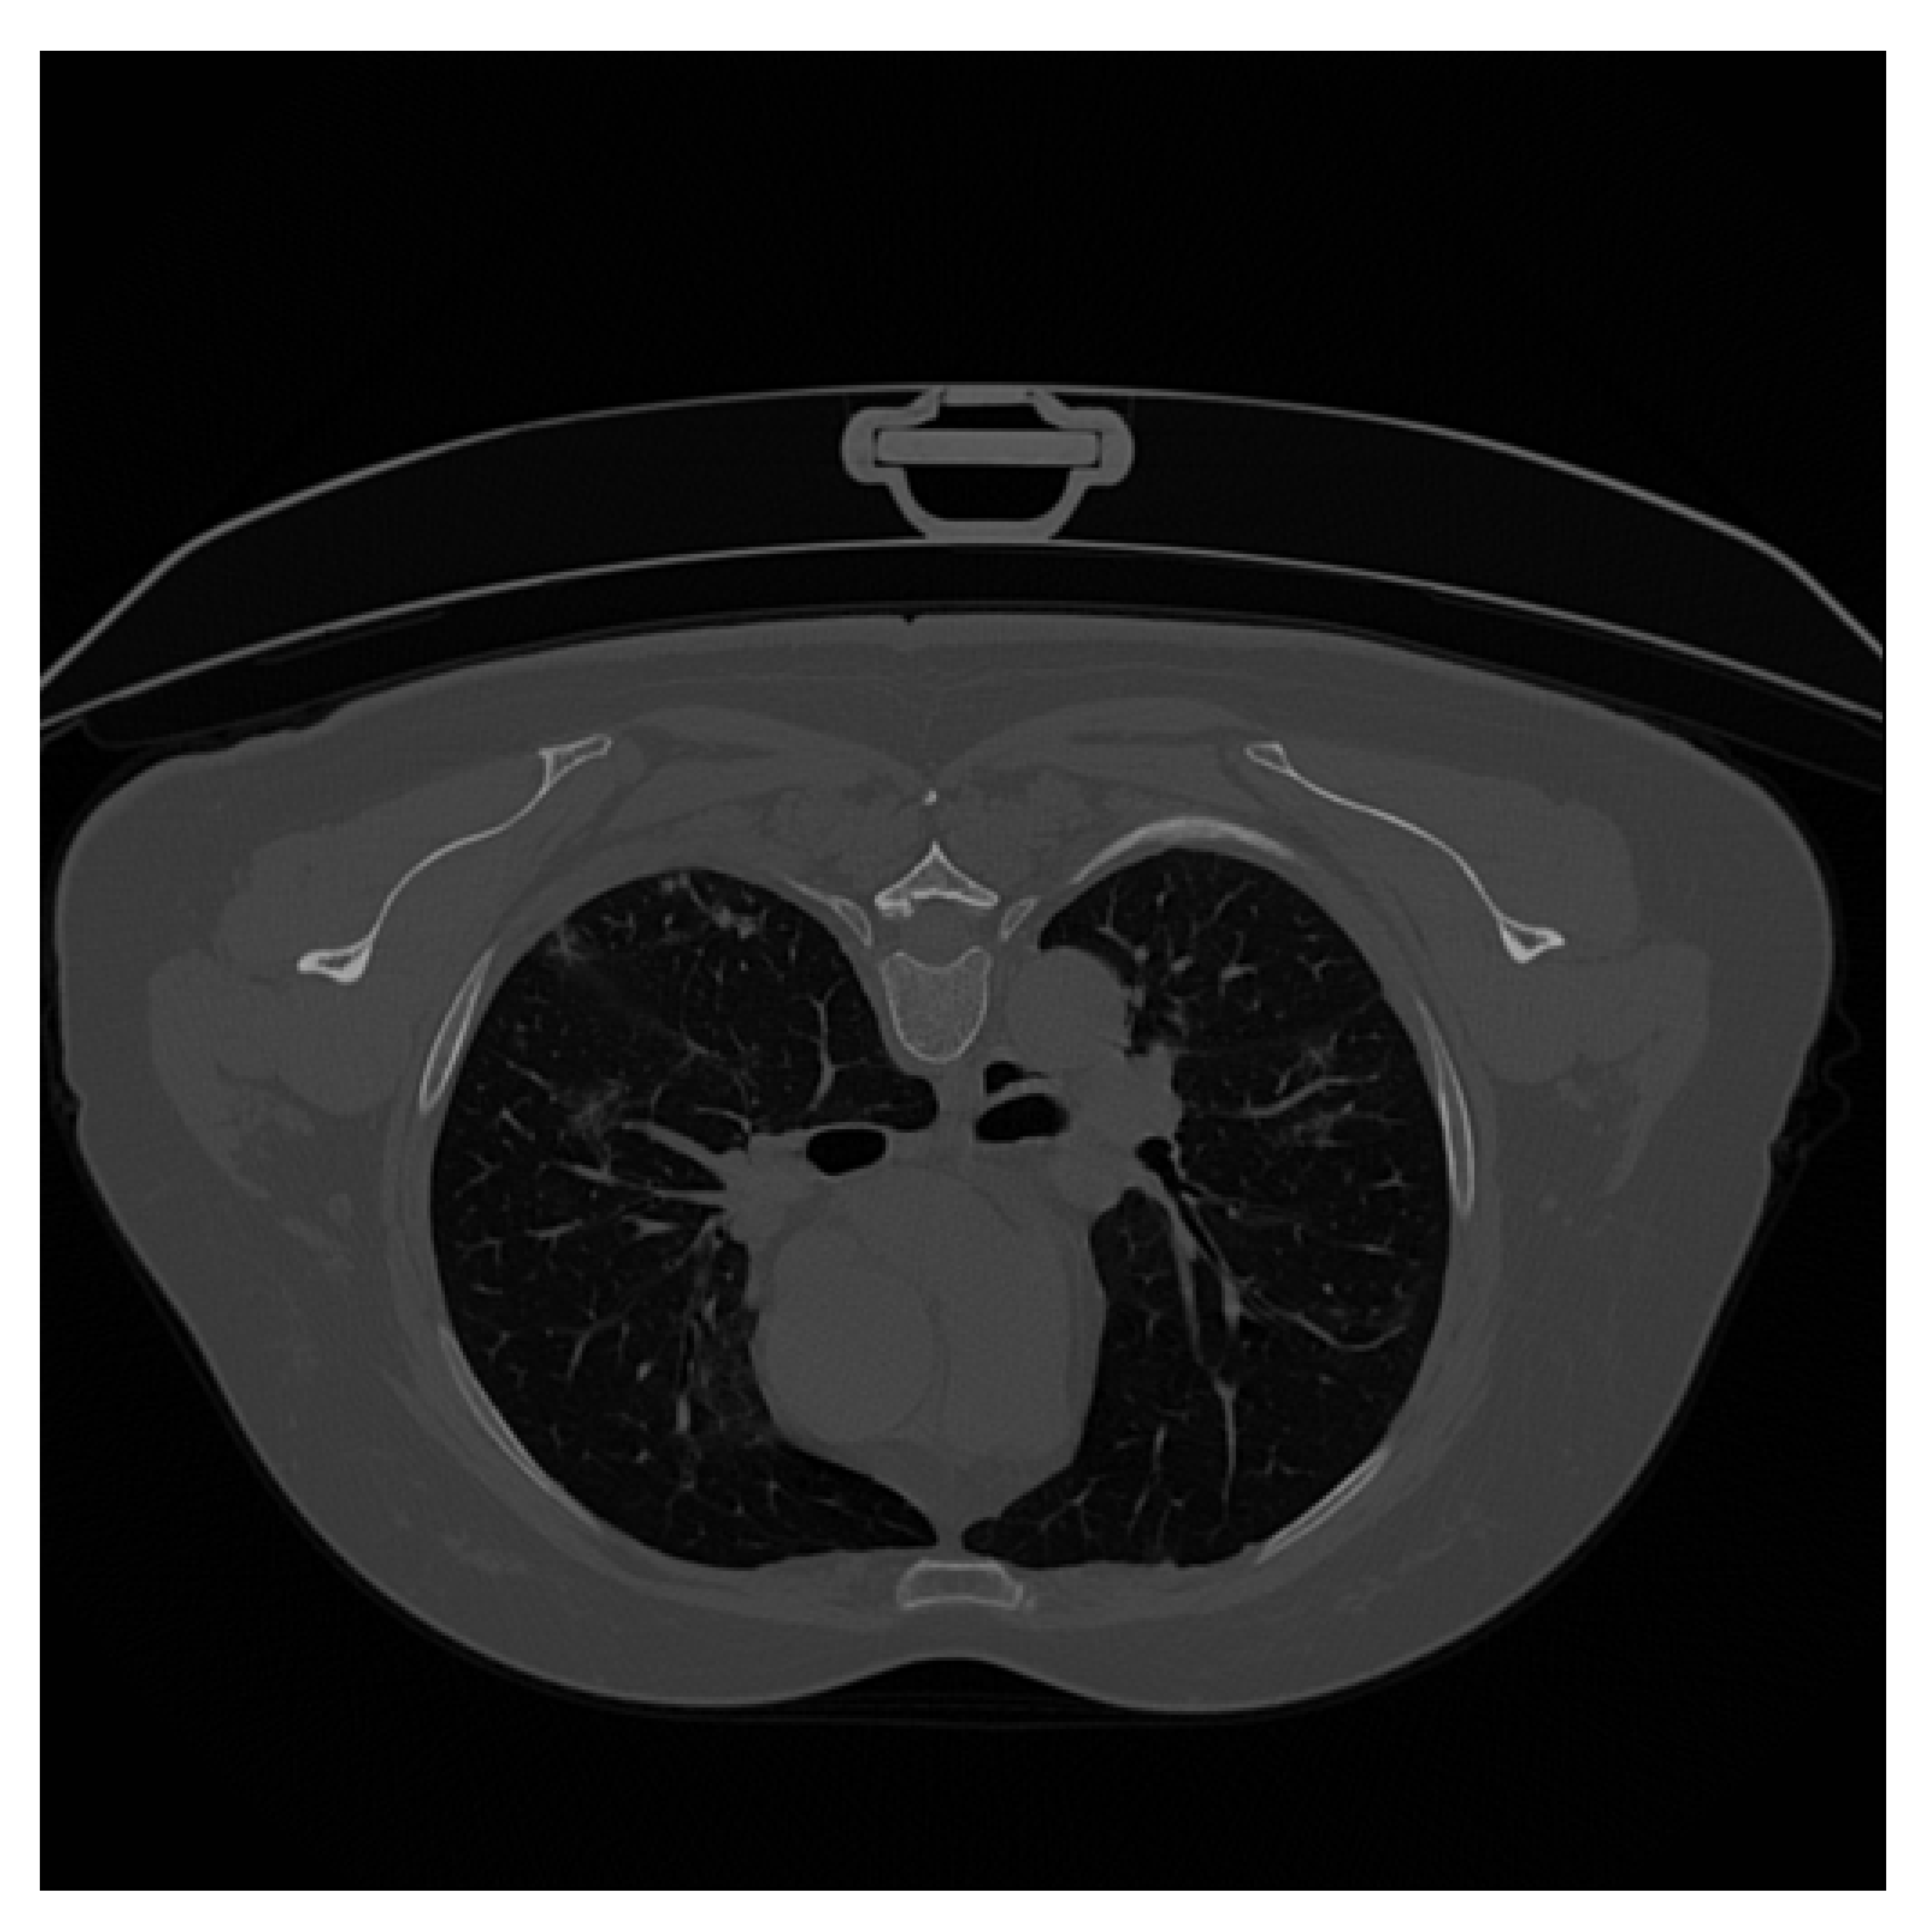

| Original CT Scan | Lung Mask | Infection Mask | Lung and Infection Masks |

|---|---|---|---|

![]() | ![]() | ![]() | ![]() |